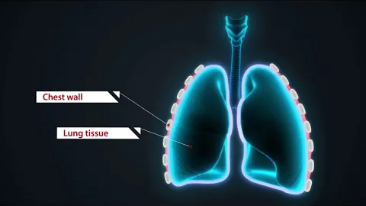

Assim como o n├Łvel de qualidade de imagem premium, o Resona 7 tamb├®m melhora as capacidades de investiga??o cl├Łnica com o revolucion├Īrio Fluxo V para avalia??o hemodin?mica vascular e a aquisi??o de plano mais inteligente do conjunto de dados 3D para diagn├│stico CNS fetal. Combinando a opera??o mais intuitiva baseada em gesto de multi-toques e todos os recursos cl├Łnicos essenciais, Resona 7 est├Ī realmente conduzindo novas ondas na inova??o de ultra-som.